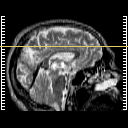

Click on sagittal image to select slice. Click on thin tickmark to change timepoint, or thick tickmark for overlay.